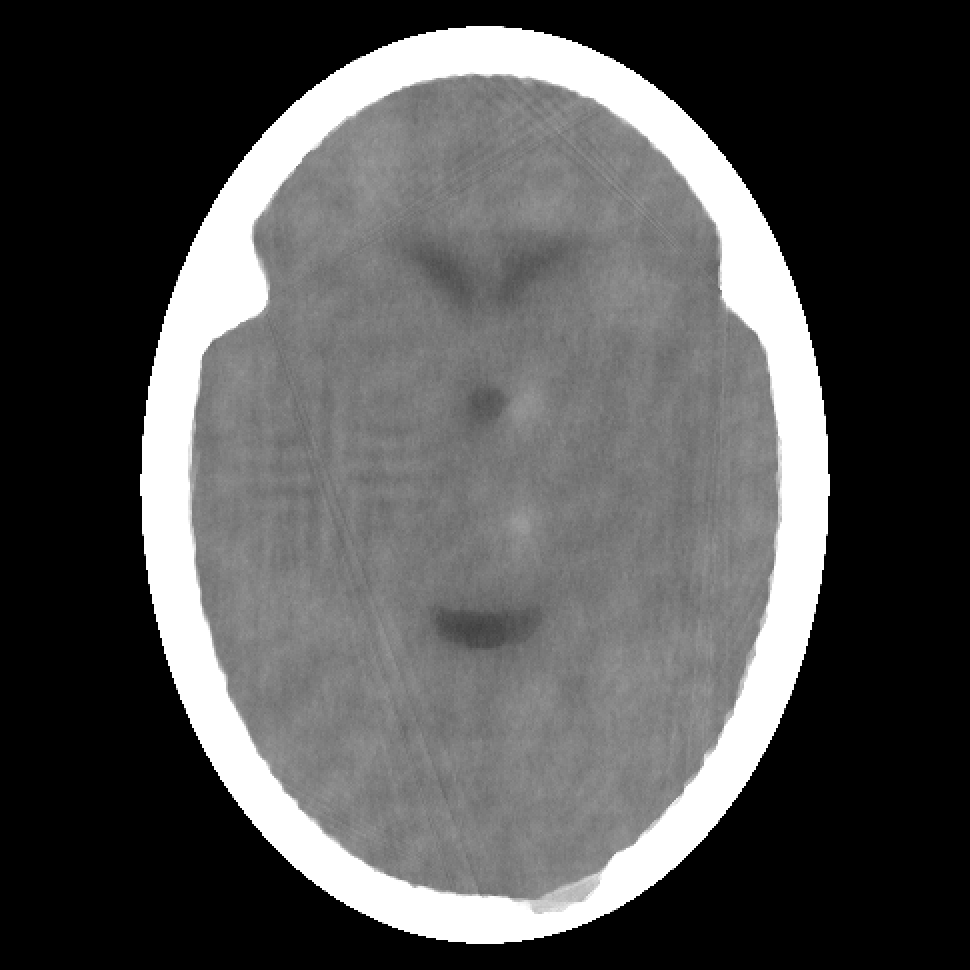

Figure 1: A 485×485485485485\times 485 digitization of a phantom based on the distribution of x-ray attenuation in units of cm-1 within a transaxial slice of the human head. We display in (a) 0.000 as black and any value that is 0.6241749 or greater as white, in (b) 0.20400 as black and any value that is 0.21675 or greater as white. The latter mapping of values into displayed intensities is used for all the images shown below.

In this section we report on experiments with phantoms based on a transaxial slice of the human head. The phantoms mimic an actual medical image; for details, see Sections 4.3 and 4.4 of [1]. The various phantoms differ from each other by the random assignment of local inhomogeneities and, more importantly, by a random introduction of small “tumors”; see Section 5.2 of [1]. A 485×485485485485\times 485 digitization of one such phantom (produced by the software SNARK14 [26] in the manner specified in [1]) is shown in Fig. 1. In this, and in all of the other digitized images shown in this paper, the length of a side of a pixel is 0.0376 cm.